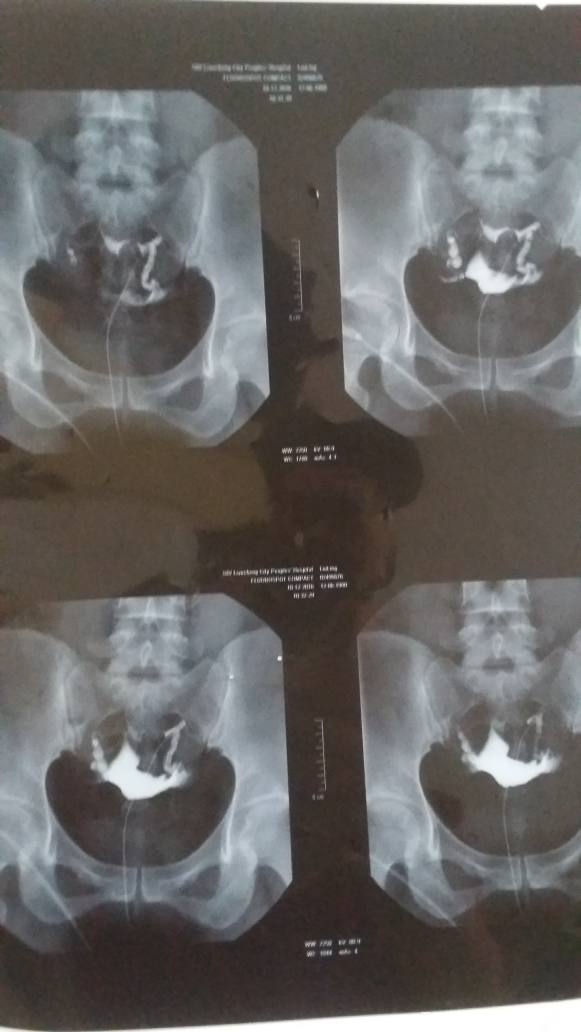

15年9月份自然流产一次,当时二胎没有放开也没有保胎。现在备孕一年未孕。请大夫看下片子。找的大夫说左侧。左侧不好右侧尤其不好,但是报告上写的左侧通畅右侧通而不畅。到底是怎么回事呢。谢谢了。36岁,要二胎。其他检查正常,月经周期正常。

你好,左侧好些,有机会怀孕

嗯!左侧应该是通畅的!

您好,左侧基本是通畅的,有机会怀孕。